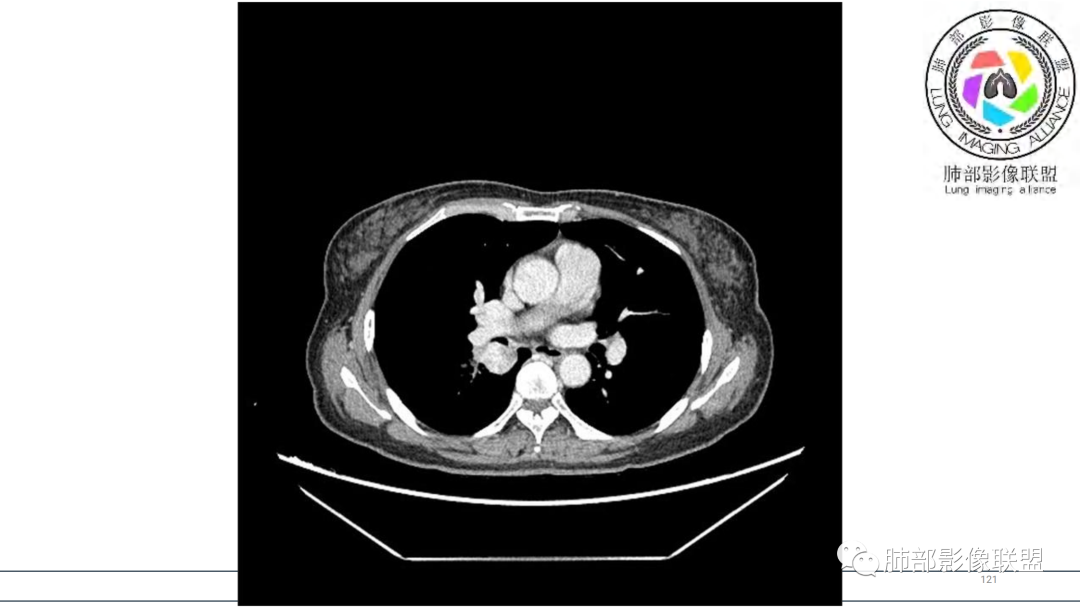

2.右肺下叶及中间段支气管后方类圆形块影,边界较清楚,未见分叶及毛刺,病灶部分突入支气管腔内(冰山一角),局部管腔狭窄,相应肺叶未见片影或体积变化。

3.块影密度均匀,未见液化坏死及钙化,渐进性强化,强化显著。

中青年女性,支气管管腔内外肿块(“冰山征”),边界较清楚,强化显著,未见阻塞性肺不张,尽管未出现“类癌综合征”临床表现,仍然符合典型类癌影像学表现。